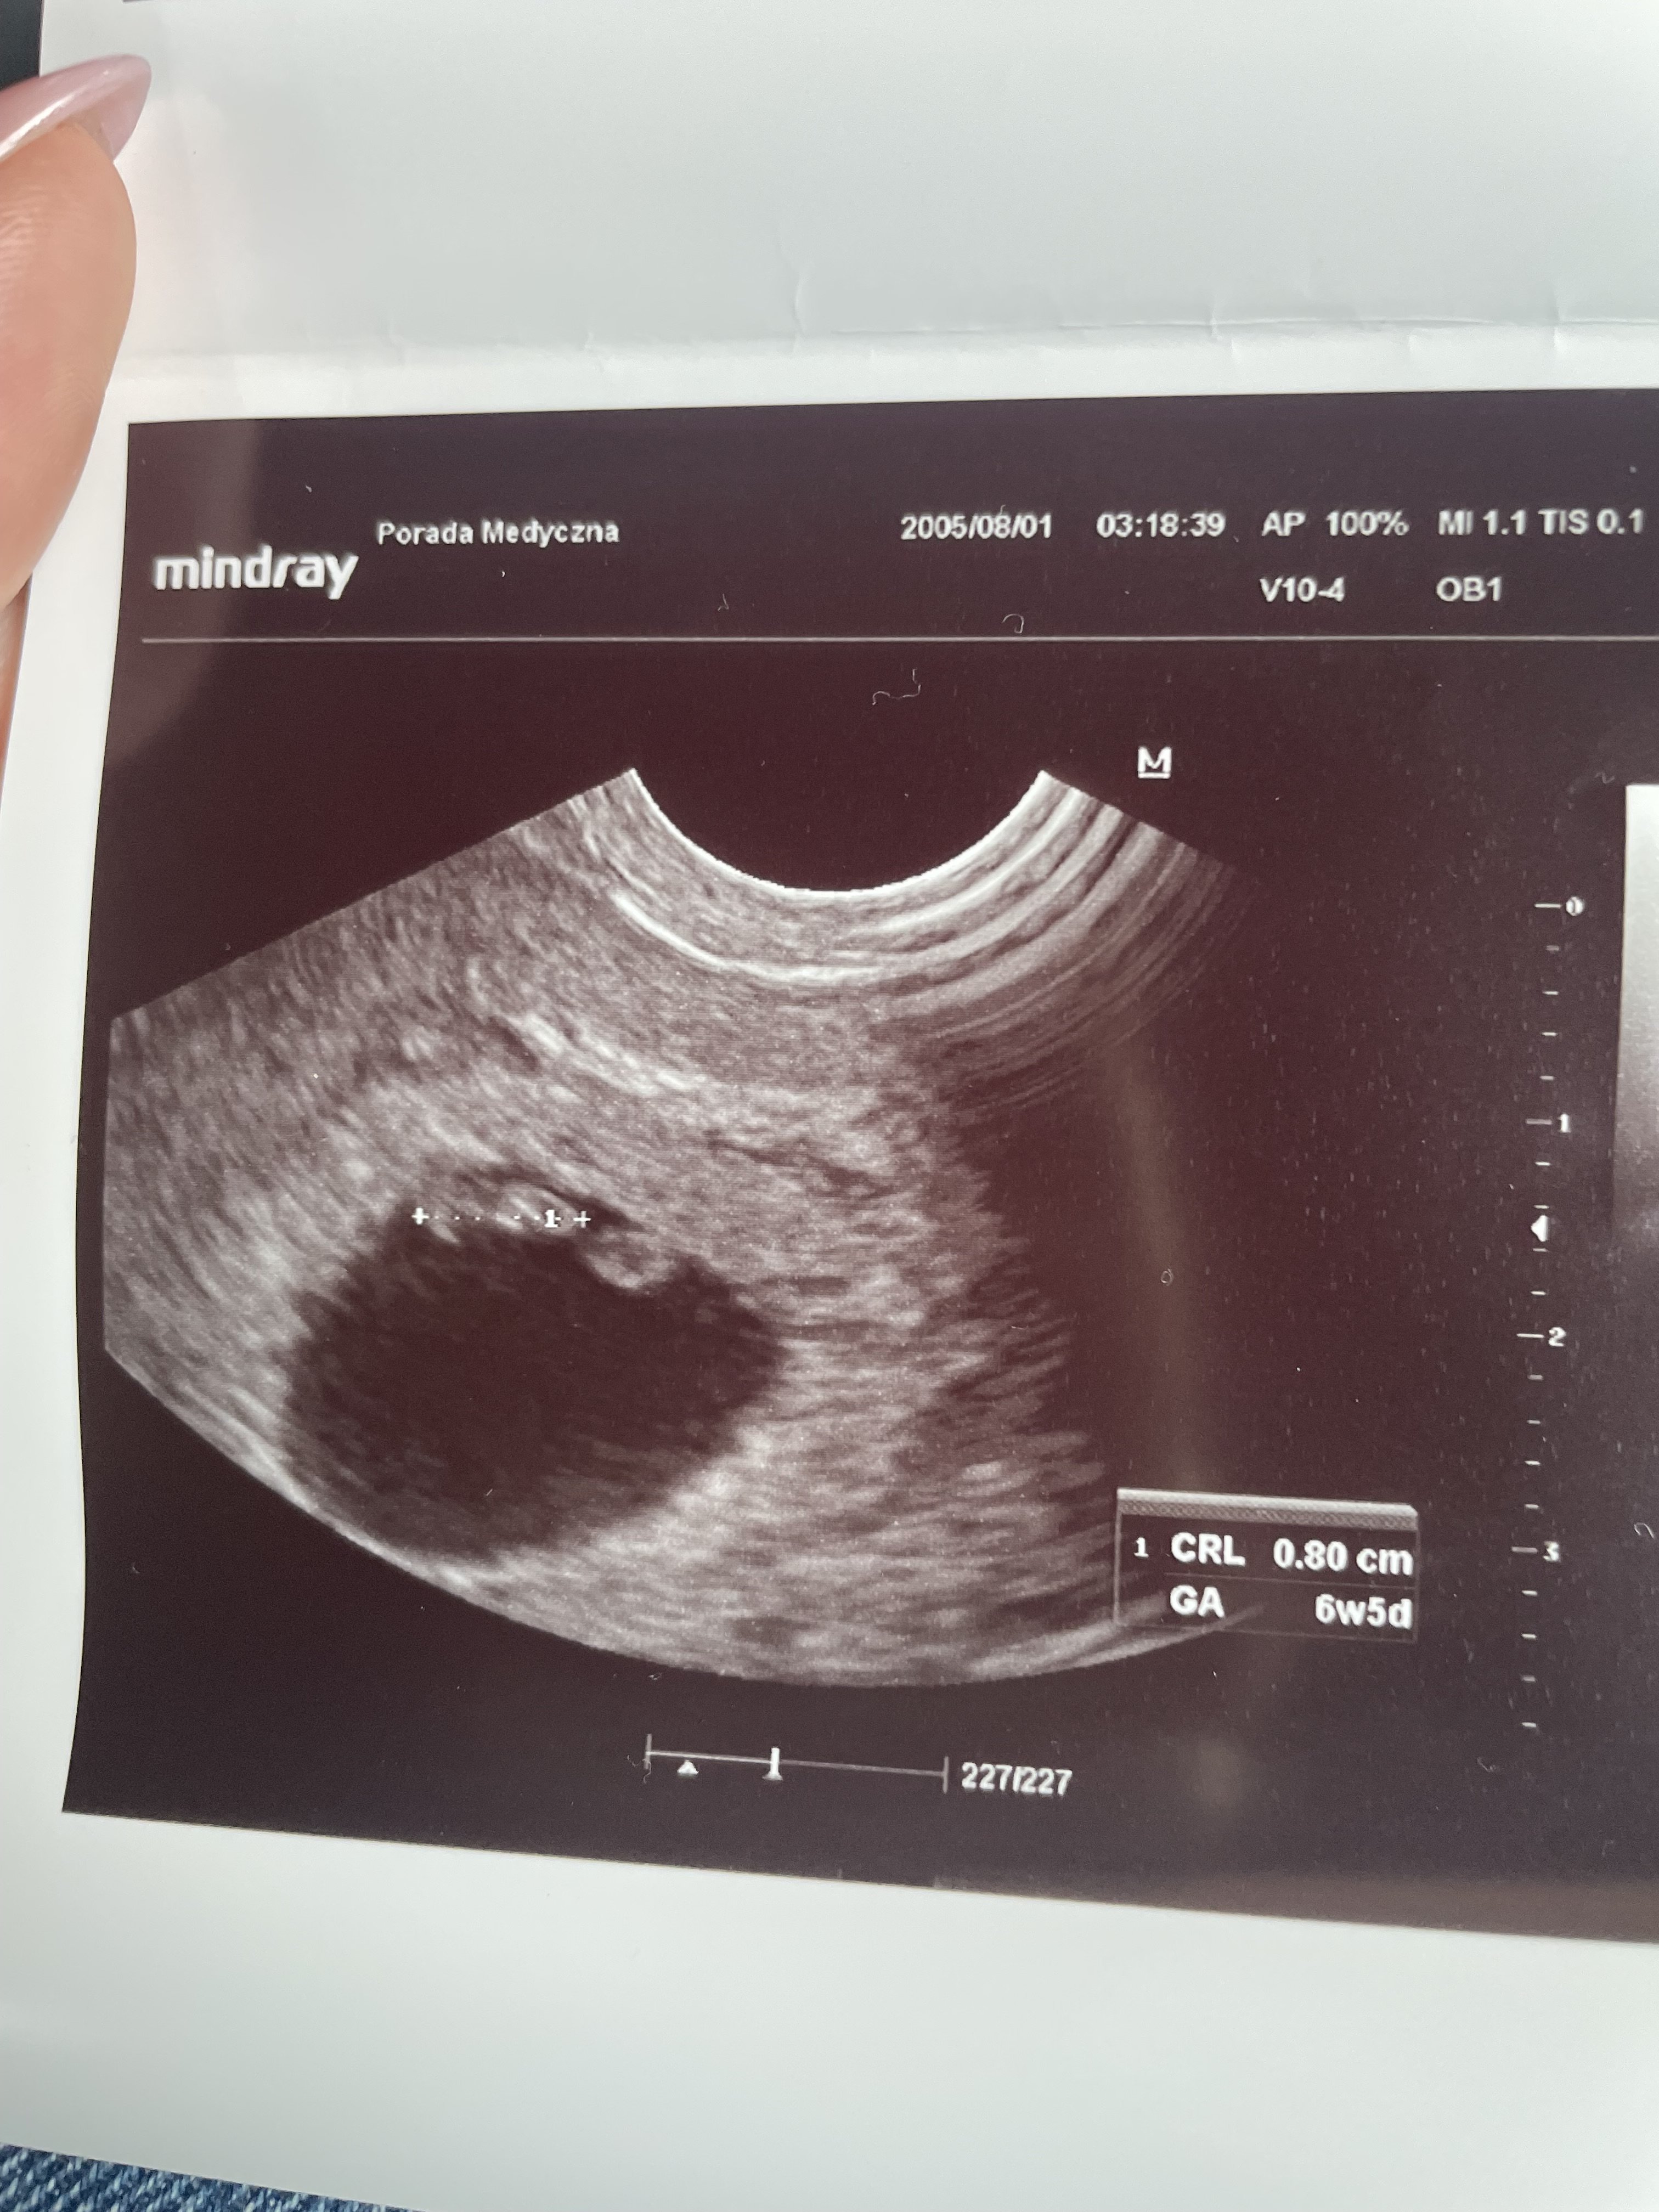

Ja już po! Bije serduszko jak złoto ♥️ teraz i tak będę drżeć do kolejnej wizyty przez tego półpaśca. No ale na ten moment mam 0,8cm bejbika w brzuchu 🥹

IMG_3461.jpeg